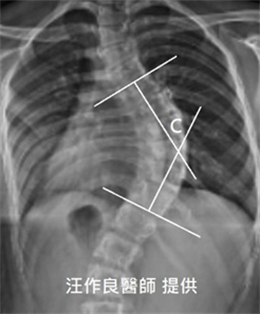

一般患者或家長只關心X光片的側彎角度(即Cobb角)(如下圖中角度C),卻往往忽略體態的變形。X光片Cobb角固然是追蹤脊椎側彎惡化或改善的重要參數,但由於脊椎側彎是脊椎的三維變形,以下3個體態參數也是讓脊椎側彎惡化風險提升的重要因子,因此也是非手術矯治的重點: